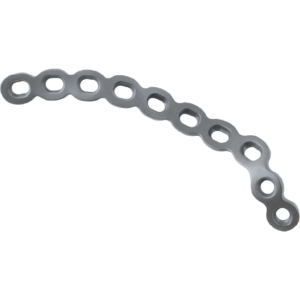

Curved Reconstruction Plates